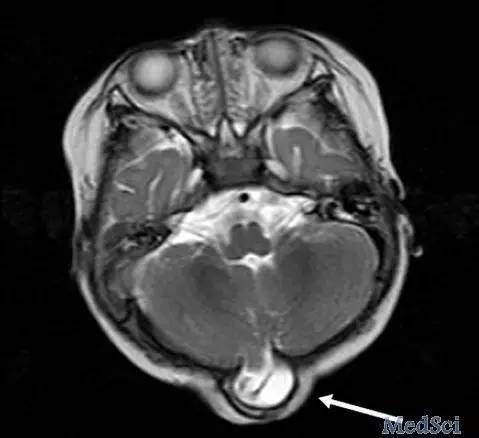

诊断:枕部脑膨出

讨论:MRI显示患儿枕骨局部缺损,脑脊液充满的囊腔加上部分脑组织从缺损部位向外膨出形成疝,表明患儿存在脑膨出问题(图 2⇓)。

脑膨出是一种罕见的先天性畸形,由于颅骨缺损导致脑膜和脑组织向外膨出形成疝。这是一种神经管缺陷,活产婴儿的发病率为1/10000 到5/10 000,约75%发生在枕部。颅裂和脑膨出的患儿应接受手术修复治疗。手术治疗的目的是切掉囊并将有功能的神经组织重新复位和保护。预后取决于脑膨出发生的解剖部位,膨出的脑组织的体积,以及是否存在其他共存畸形。既往一项研究发现,枕部脑膨出的患者较其他类型的脑膨出预后差。建议所有的孕妇利用产前超声检查进行筛查。越来越多应用于英国教学医院的胎儿磁共振成像也可以诊断这种疾病。此外,怀孕前和怀孕的早期补充叶酸或可有助于预防此类缺陷的发生。磁共振成像可在胎儿出生后确诊该病。